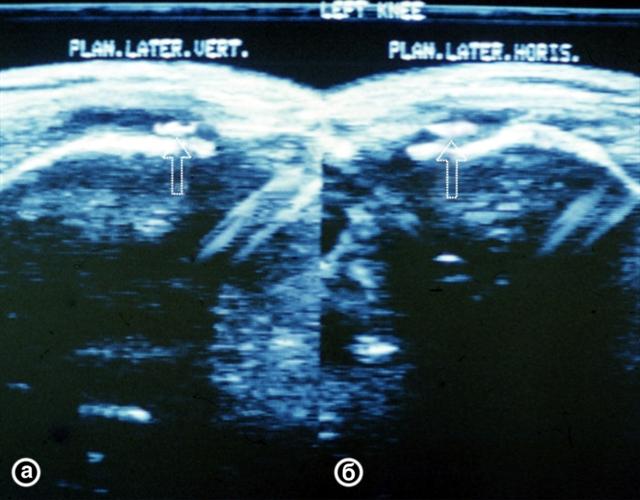

Рис. 26. Ультрасонограмма коленных суставов (продольный медиальный срез) при паракапсулярном разрыве внутреннего мениска (а) и в норме (б): зона сниженной эхогенности в месте разрыва указана стрелкой.